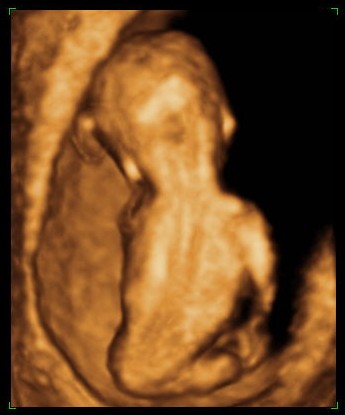

Gesunder Embryo mit unauffälligem Rücken